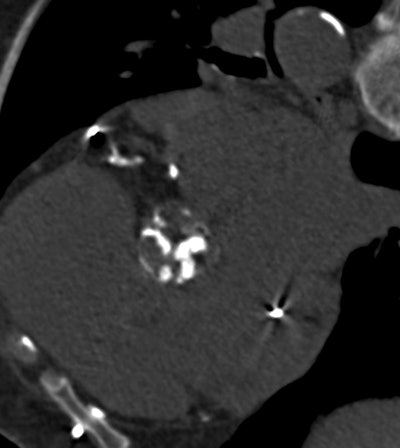

Aortic valve calcification is easily discernible at MDCT in a patient with extensive calcifications. Image courtesy of Dr. Maurice Enriquez-Sarano.Common condition